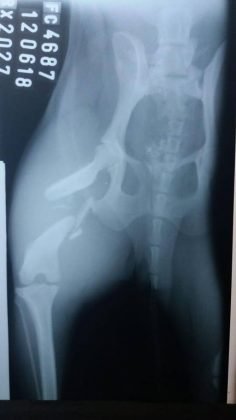

Colabore com a cirurgia da Belinha

Belinha foi salva por uma protetora e doada para uma familia no dia 1º do mês passado. Ela ‘fugiu’ no mesmo dia e uma pessoa informou que a ‘menina’ havia sido atropelada em frente a um posto de combustíveis, no bairro São João Margem Direita, dois dias depois. Desde o seu sumiço ocorreu uma mobilização para encontrá-la. No último dia 12, ela foi levada ao veterinario, feita uma radiografia e constatado uma fratura completa em espiral na pata direita. A situação é delicada. Essa ‘guerreira’ tem tomado remédios para dor. Agora, ela está em Criciúma e é necessário arrecadar dinheiro para o tratamento. Ainda não se sabe o valor total, mas até o momento o custo foi de R$1.1. Acredita-se que o montante final do tratamento será de R$1.7. Além disso, há os custos com as medicações e toda a recuperação. Quem puder ajudar entrar em contato com a Simone pelo telefone 48- 99191-9137. Qualquer valor ajuda muito, se cada um doar um pouquinho no final teremos o montante completo. Muito obrigada!